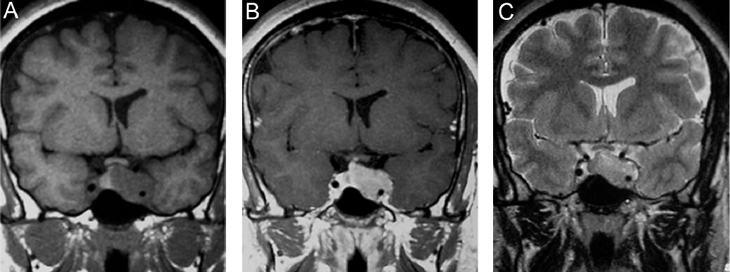

Anatomía normal de la glándula pituitaria

En los recién nacidos, la glándula tiene un borde superior convexo y presenta hiperseñal homogénea en secuencias T1w (Figura 3A). Durante el primer año de vida la adenohipófisis cambia su señal, pero se mantiene un foco de hiperseñal posterior donde se ubica la neurohipófisis (Figura 3B). A partir de los dos años de edad adquiere una altura < 6 mm, tamaño que se mantiene hasta la pubertad, período en que aumenta alcanzando en promedio 8 mm en niños y 10 mm en niñas, medidas que se mantienen en los adultos jóvenes17 (Figuras 4A, 4B y 4C). Durante el embarazo la hipófisis alcanza su mayor tamaño, con 12 mm de altura durante el último mes de gestación y en la primera semana posparto (Figura 5). La adenohipófisis aumenta en un 30% su tamaño, alcanzando su máximo volumen al tercer día posparto18, como resultado de la hipertrofia e hiperplasia de los lactotropos inducida por los estrógenos de la placenta. La neurohipófisis pierde su foco de hiperseñal durante el tercer trimestre, aunque las dimensiones del tallo hipofisiario y de la neurohipófisis no se modifican durante el embarazo.

Figura 3A. Corte sagital, secuencia T1w. Glándula pituitaria en un recién nacido, muestra hiperseñal homogénea normal a esta edad.

Figura 3B. Corte sagital, secuencia T1w. Glándula pituitaria en lactante de 2 meses, muestra disminución de la hiperseñal de la adenohipófisis.

Figura 4A. Corte sagital, secuencia T1w. Glándula pituitaria normal en adulto joven (27 años), muestra foco posterior de hiperseñal de la neurohipófisis (punta de flecha); la señal de la adenohipófisis es similar a la de la protuberancia.

Figura 4B. Corte sagital, secuencia T2w.en el mismo paciente, la glándula pituitaria, muestra la neurohipófisis con leve hiperseñal (punta de flecha); la señal de la adenohipófisis es también similar a la protuberancia en esta secuencia.

Figura 4C. Corte sagital, secuencia T1w post inyección de Gadolinio. La glándula pituitaria, muestra refuerzo normal incluyendo el tallo pituitario; en el cerebro solo se refuerzan las estructuras vasculares.